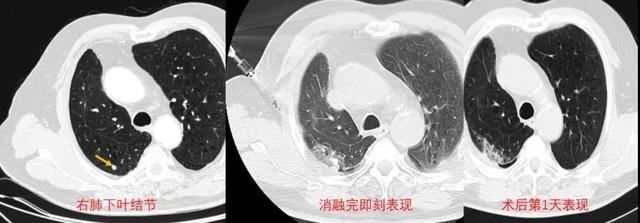

在医务科、放射科的支持下 , 8月18日 , 手术如期举行 。 CT引导下 , 胡波副主任医师顺利穿刺、精准刺入肿瘤病灶 , 释放微波后 , 肿瘤被逐渐消融 , 手术仅用时半个小时 。 由于手术只需局部麻醉 , 病人全程清醒无痛苦 , 术后即刻及术后第一天复查胸部CT均提示肺肿瘤消融范围非常满意 。

△肺转移瘤发现到治疗后CT表现